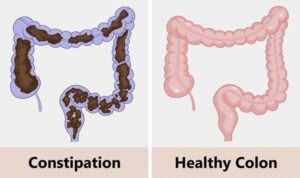

The easiest ways to detoxify and boost digestion, and how to naturally cleanse the intestines and stomach, a natural colon cleanse might be beneficial for you if you suffer from low energy, headaches, fatigue, or weight gain. Colon cleansing involves the use of tea, enzymes, colon irrigation, and other techniques to remove impurities from the large intestine.

Colon cleansing is a common complementary treatment aimed at purifying the colon from waste and toxins. Except for the systems recommended by doctors, there is no scientific data supporting the use of colon cleansing techniques.

It means colon cleansing; the practice of colon cleansing has been around for a long time. Its popularity has grown recently. You can also refer to the colon as the large intestine or the intestines. Where a part of the digestive system digests food and transports waste to the rectum. Usually, the colon is cleansed before medical treatments, such as a colonoscopy.

When you cleanse the colon, what comes out

The one that exits, where waste and toxins leave the body. The results of one study indicate that colon cleansing before a colonoscopy removes about 1.2 kg of waste. But it is important to consider that this mainly refers to water and waste.